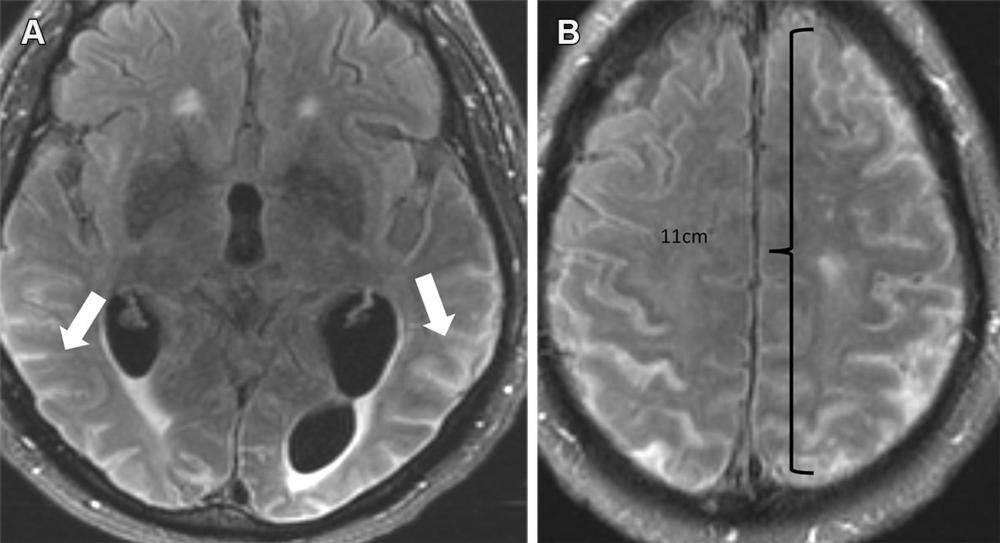

Figure 7. Severe ARIA-E (edema) in a 69-year-old woman receiving aducanumab therapy for AD with headaches and word-finding difficulty. (A, B) Axial MR images of the brain show multifocal subcortical edema (arrows) with FLAIR hyperintensity (A) and increased diffusion on the apparent diffusion coefficient (ADC) map (B), with a few areas measuring more than 10 cm. (C) Axial follow-up MR image 4 months later shows near-complete resolution of signal intensity changes. ARIA-E is most common in the occipital lobes (as in this case) and mimics posterior reversible encephalopathy syndrome (PRES) at imaging.

Figure 10. Severe ARIA-E (effusion) in a 76-yearold man with worsening headaches receiving aducanumab therapy for AD. Axial brain MR images from December 2021 (3 weeks after full dose) show multifocal exudates along the sulci with FLAIR hyperintensity (arrows in A), measuring more than 10 cm (severe) with subtle leptomeningeal enhancement (B). Treatment was suspended, and complete resolution of effusion was noted after cessation of therapy.